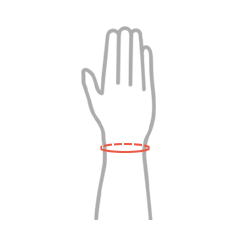

| Rozmiar | Obwód nadgarstka | Sposób dokonywania pomiaru |

| M | min 13 – max 17 cm |  |

| L | min 17 – max 24 cm |